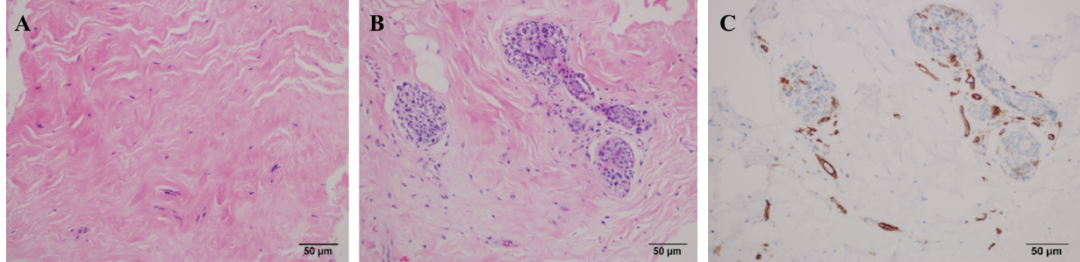

图2 3D打印支架移植到人体内一年后的穿刺活检结果。(A-B)3D打印支架内组织的HE染色结果;(C)3D打印支架内组织的CD31免疫组织化学分析。在支架内部/周围观察到的纤维结缔组织、成纤维细胞和血管表明了支架的良好生物相容性。

术后结果显示,植入物在术后的不同时间均能够维持自然且与对侧对称的乳腺外形。所有患者的乳头和乳晕区域均未出现皮瓣坏死或缺血情况;无患者报告功能性肢体功能障碍。术后1个月,12位患者有肿胀、疼痛或异物感,三个月后症状消失。术后1年组织学分析显示,支架内部及周围存在纤维结缔组织、成纤维细胞和血管。伴随着支架内的自体组织再生,3D打印支架在体内逐渐降解,平均降解率在12个月时为54.07%,24个月时为74.48%,36个月时为86.94%,48个月时为87.36%,60个月时为92.76%。